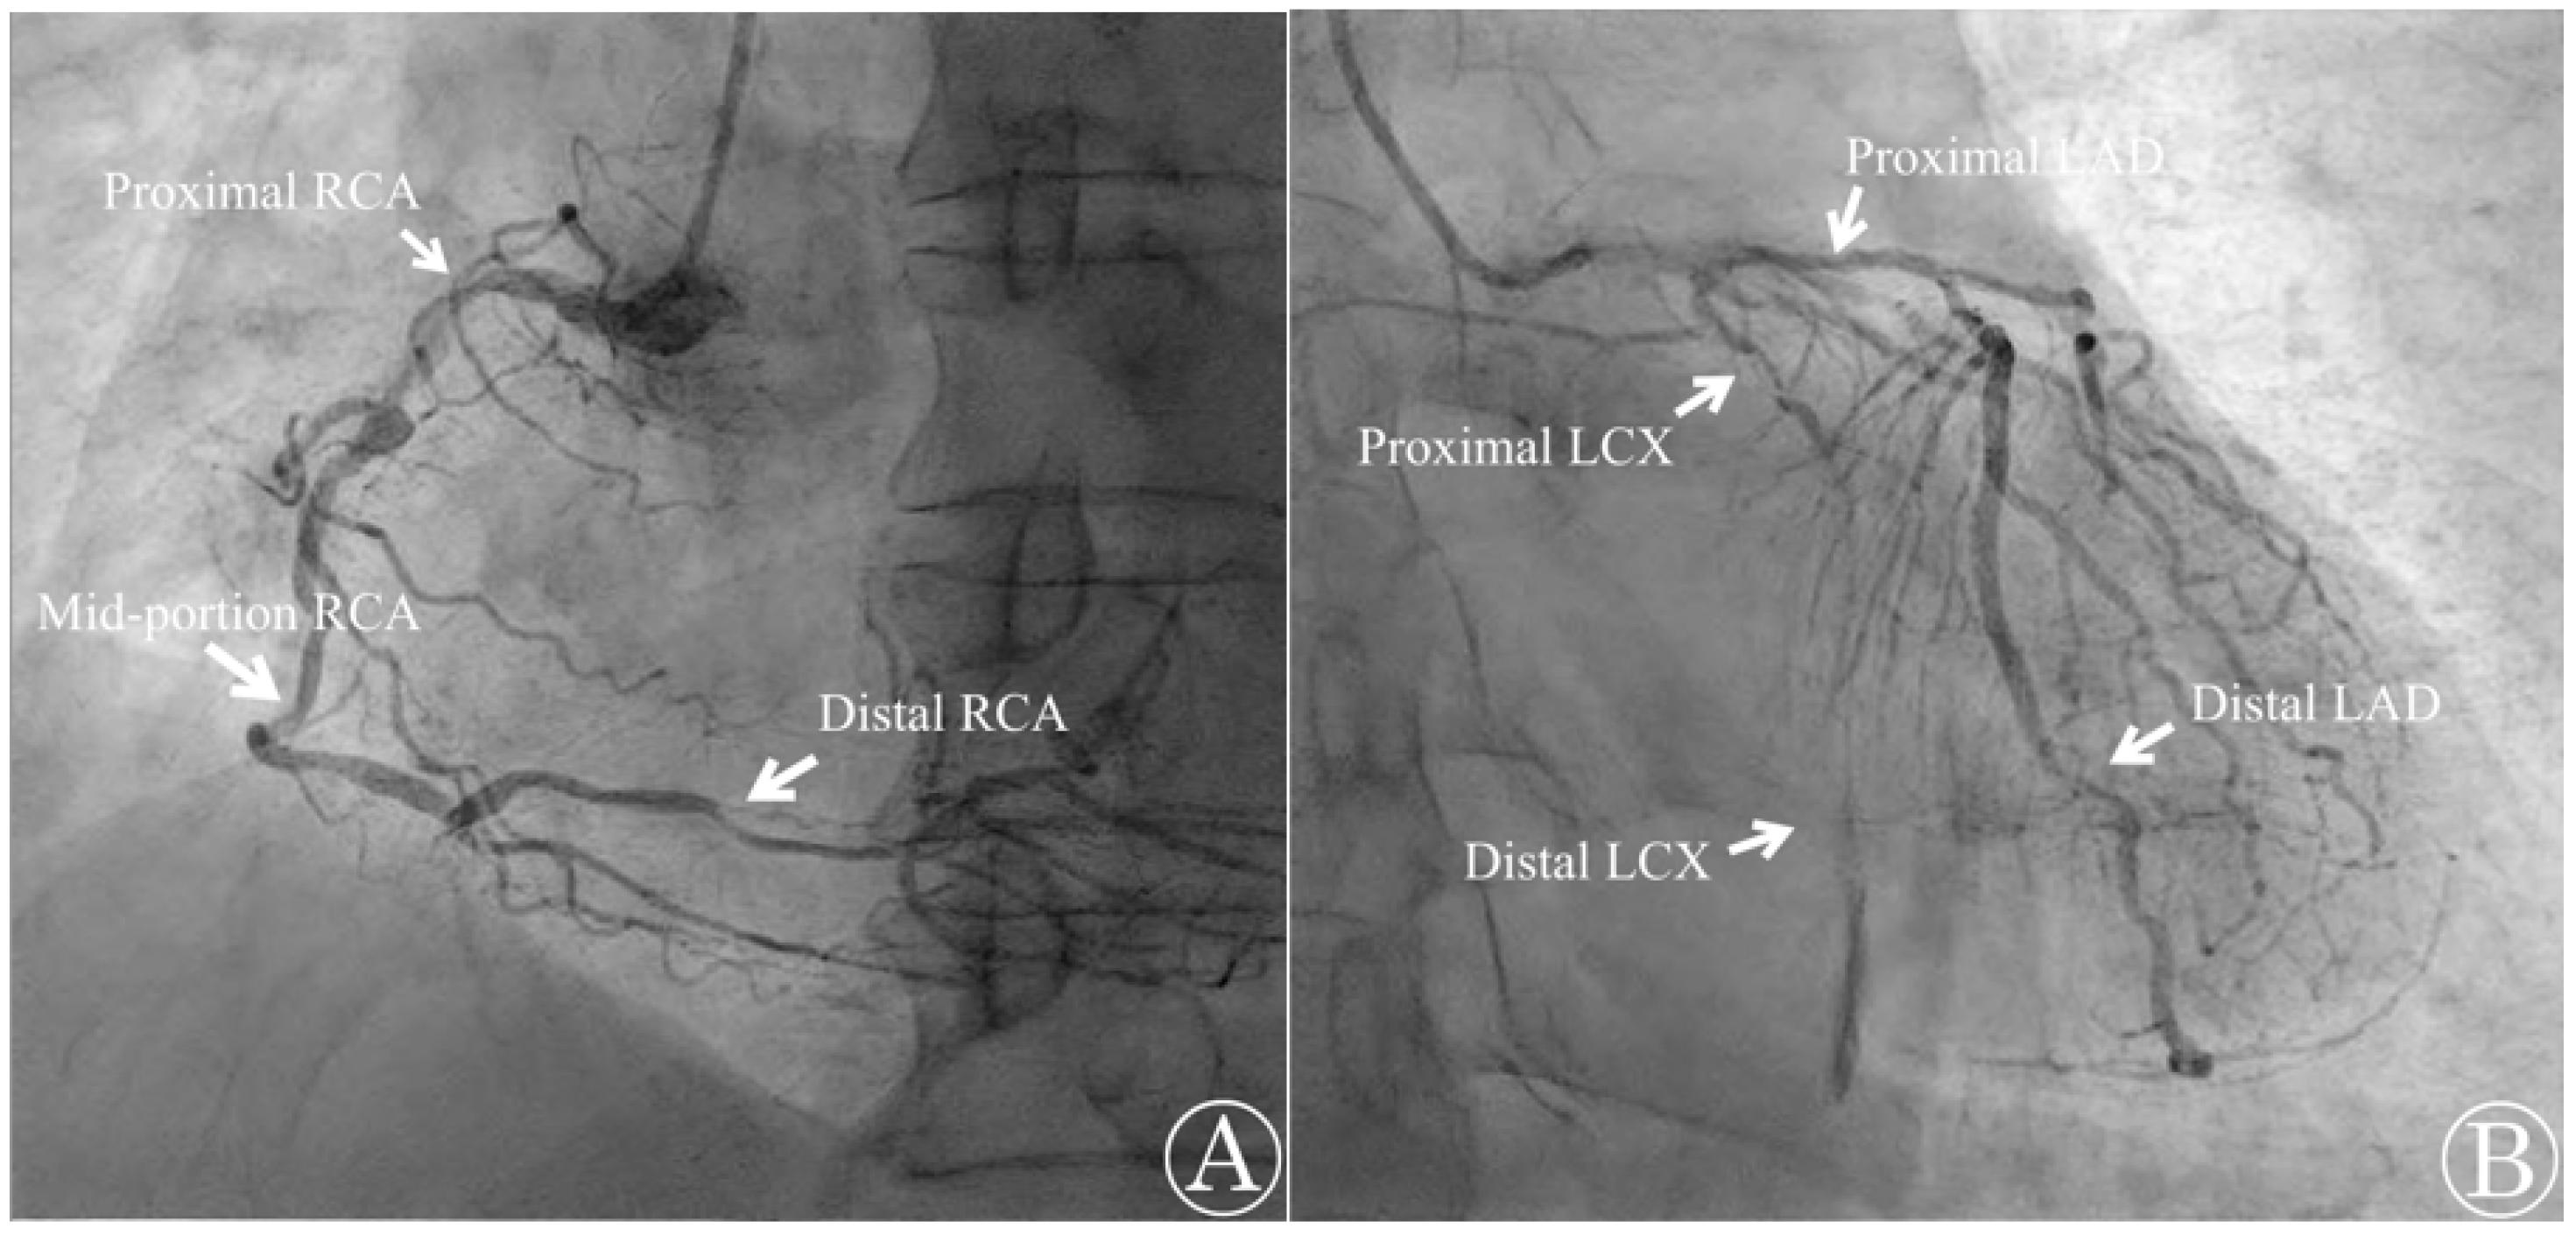

Emergency TTE, coronary angiography (CAG), and computed tomography angiography (CTA) were performed at the cardiology center. The TTE revealed that the patient’s ventricular function was preserved with an LVEF of 68% and did not show any valvular abnormalities. However, the CAG report indicated that the patient had three-vessel CAD with multiple diffuse stenoses. The right coronary artery, left circumflex artery, and left anterior descending artery were found to have stenoses of up to 90%, 100%, and 80%, respectively (Figure 4). The percutaneous coronary intervention was not possible due to the complexity of the case and the presence of three-vessel CAD with stenoses above 70%. The CTA also revealed diffuse atherosclerosis, with multiple atheromas along the thoracoabdominal aorta, and severe (>70%) intramammary artery stenosis. Cardiac biomarker levels that were sampled in the operating room later confirmed elevated cardiac troponin I (cTnI) and lactate dehydrogenase (LDH) with levels measuring 21.5 pg/mL and 225 U/L, respectively. Creatinine kinase-MB (CK-MB) was at 2.82 ng/mL, which was within the normal limit. The patient was diagnosed with type 2 MI and later transferred to the cardiothoracic surgery department to undergo elective CABG surgery a week later. The surgery was uneventful, and the patient was discharged 3 weeks later after recovery.

Figure 4. Emergency coronary angiography shows occlusion in multiple sites. (A) The right coronary artery (RCA) was found to be occluded by 90% at the proximal segment, 70% at the mid-portion, and 80% at the distal segment; (B) the left circumflex artery (LCX) was occluded by 95% at the proximal segment and 100% at the distal segment. The left anterior descending artery (LAD) was occluded 80% at both the proximal and distal portions.